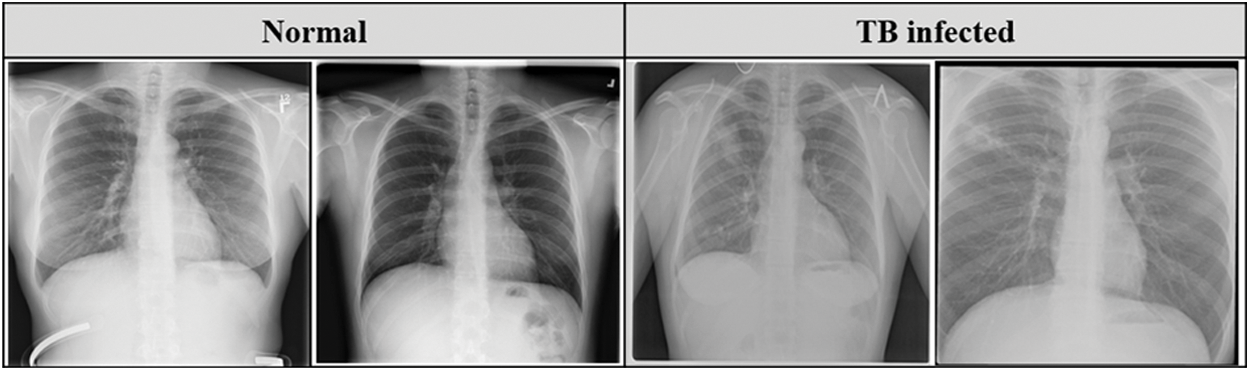

Belarus set was collected for a drug resistance study initiated by the National Institute of Allergy and Infectious Diseases, Ministry of Health, Republic of Belarus. This dataset consists of 306 CXR images collected from 169 patients. Fig. 2 describes the sample of the CXR images used in this study.

Figure 2: Sample CXR images from the datasets